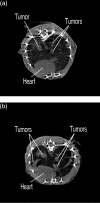

Figure 7

MicroCT lung scans of (a) living and (b) euthanized BALB/c mouse seeded with EMT-6 lung tumors.